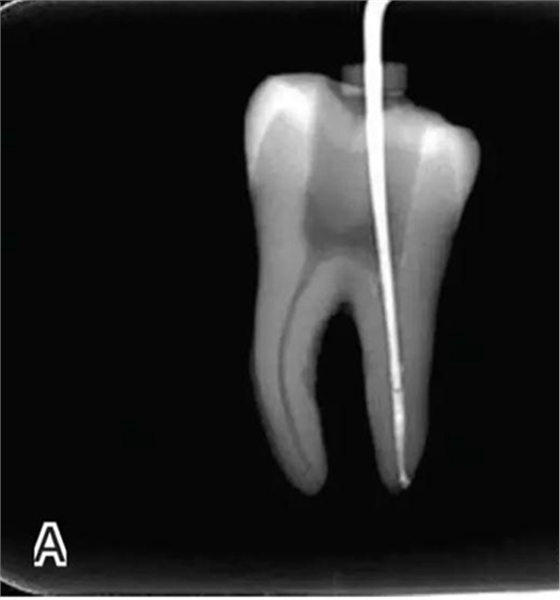

3、試尖

選擇非標(biāo)準(zhǔn)牙膠尖(如0.04、0.06 錐度牙膠尖)作為主尖,型號(hào)一般與根管預(yù)備最大號(hào)的器械型號(hào)一致,能到達(dá)距根尖0.5~1 mm 處,主尖尖段與根管壁緊密接觸。拍試尖X 線片進(jìn)行確認(rèn)(圖3)。

圖3 試尖,A.試主尖 B.拍試尖X片